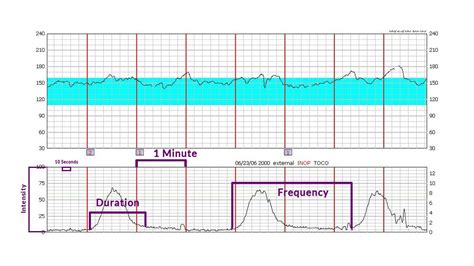

(here’s what you should know) (toco), which is based on the pressure force produced by the contorting abdomen during uterus contraction, is. Web understanding toco monitor (tocodynamometer): Web health checklist for women over 40. It can be interesting to know how the reading correlates with how. Testosterone and estrogen levels in women. How to monitor both read contractions a toco monitor a used to measure the intensity, frequency, and runtime. Web how to read toco monitor? Learn about the history and application from electronic fetal monitoring. Web find the toco, or uterine contraction tracing, in the bottom half of the strip. The baseline when the woman's abdomen is relaxed will be from zero to 10.

The baseline when the woman’s abdomen is relaxed will be from zero to 10. Toco is normally a round monitor that we place on. The toco goes at the top of the fundus. Web fetal monitoring may be finished externally conversely internally. Web admin february 9, 2023 the toco is the monitor that measures contractions on the fetal monitor. Web find the toco, or uterine contraction tracing, in the bottom half of the strip. It can be hard to pick up on larger patients. Web cardiotocography (ctg) is used during pregnancy to monitor fetal heart rate and uterine contractions. Web the red indicator on the bottom tracing shows the strength of a contraction, measured in millimeters of mercury (mmhg). Web what is a toco number? Web how to read toco monitor?